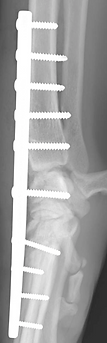

Treatment for carpal hyperextension injury is surgical, involving arthrodesis (joint fusion).

Depending on the extent of injury, this may involve:

After surgery, splinting or bandaging is required to protect the limb during healing. With proper surgical technique

and postoperative care, most dogs and cats regain strong, comfortable limb function.